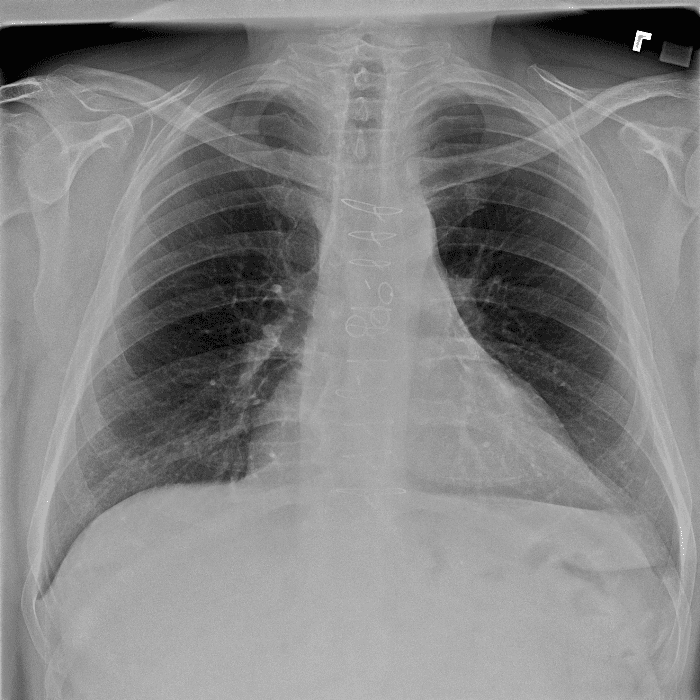

Practice Cases